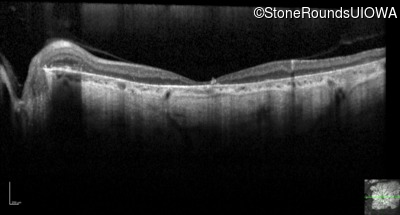

Optical Coherence Tomography - Right - 20/200 +1 sc

Exemplar / OCT Stack

OCT Stack